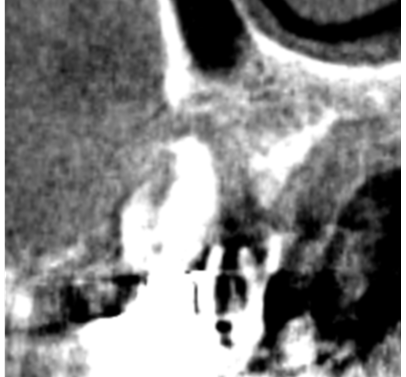

術前ではインプラントを埋入する骨組織はほとんど有りませんが、

術後完全に骨内に埋入出来ました。